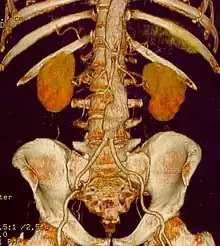

Abdominal aortic aneurysms (3,4 cm)

Abdominal aortic aneurysms (AAAs) are more common than their thoracic counterpart. One reason for this is that elastin, the principal load-bearing protein present in the wall of the aorta, is reduced in the abdominal aorta as compared to the thoracic aorta. Another is that the abdominal aorta does not possess vasa vasorum, the nutrient-supplying blood vessels within the wall of the aorta. Most AAA are true aneurysms that involve all three layers (tunica intima, tunica media and tunica adventitia). The prevalence of AAAs increases with age, with an average age of 65–70 at the time of diagnosis. AAAs have been attributed to atherosclerosis, though other factors are involved in their formation.[7]